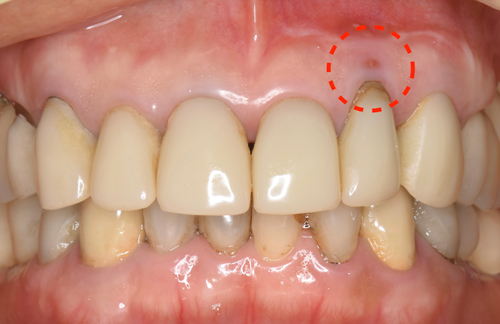

患者様はインプラントを選択され、抜歯から10ヶ月後の今月、無事にインプラントがセットされました。

クリスマス前に届いた綺麗に仕上がった前歯をセット致しました。完璧な仕上がりに、とても喜んで下さいました。